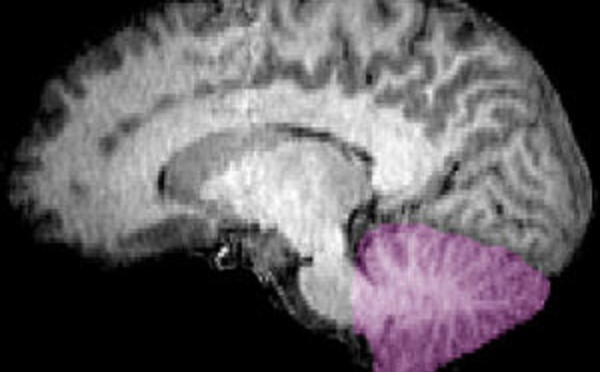

Hasta ahora, se pensaba que el neocórtex o "corteza nueva" era la región del cerebro más vinculada a las capacidades cognitivas avanzadas de nuestra especie. Sin embargo, se ha descubierto que la evolución del cerebelo, una región del encéfalo relacionada con la motricidad, evolucionó seis veces más rápido de lo previsto, posiblemente potenciando nuestra inteligencia técnica.